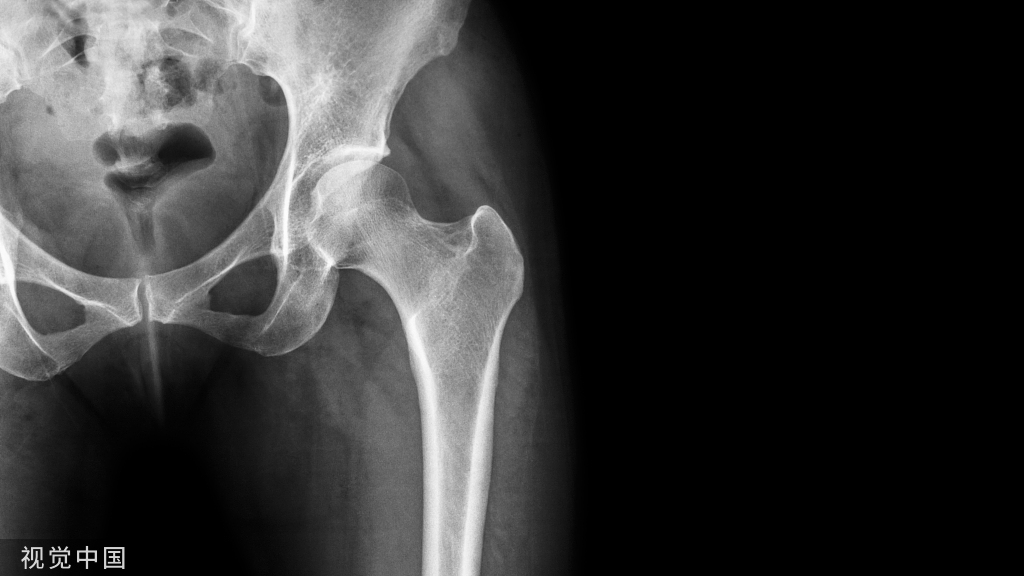

股骨颈骨折

股骨颈骨折的分型常用的有以下几种:

1、按骨折部位分为:头下型、经颈型和基底型

2、按骨折线的方向分型外展型:Pauwels角<30度,股骨头向外翻,外侧骨皮质有嵌插,为稳定型中间型:30度<Pauwels角<50度,为不稳定型内收型:Pauwels角>50度,为极不稳定型

3、按骨折移位程度的分型(Garden分型)I型:不完全性骨折II型:完全骨折,无移位 III型:有部分移位IV型:完全移位

关于GardenIII型和GardenIV型,其主要区别是看髋臼骨小梁与股骨头骨小梁有无移位。临床上还有一个鉴别方法:GardenIII型股骨头往往低头,即内翻畸形;GardenIV型股骨头完全移位,骨小梁力线与髋臼骨小梁重排,侧位x片上可见IV型往往伴有较明显的前后移位。